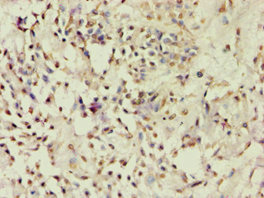

圖片:

應用范圍:ELISA, IHC

Application Recommended Dilution IHC 1:20-1:200 -